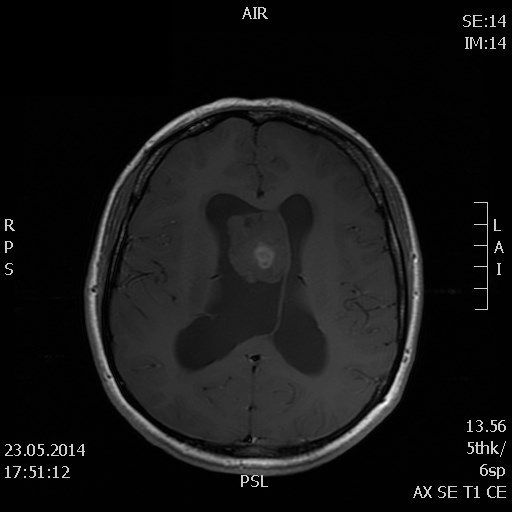

При поверхневих доброякісних пухлинах (остеома), можливе видалення тільки самої пухлини зі збереженням внутрішніх ділянок кістки. При злоякісних пухлинах необхідна максимально радикальна резекція пухлини кісток черепа з резекцією межуючих з пухлиною ділянок кістки.

Під загальним наркозом біля краю пухлини фрезою фірми Stryker накладається невеликий отвір, через який спеціальними борами та фрезами пухлина видаляється від кістки голови.

При наявності проростання пухлини в порожнину черепа виконується додаткове видалення тканини пухлини кісток черепа зі збереженням мозкової тканини та пластики оболонок головного мозку спеціальними матеріалами. При цьому використовуємо мікроскоп Carl Zeiss.

Після резекції пухлини кісток черепа, робимо пластику утвореного дефекту кістки спеціальною титановою сіткою, кістковим цементом.